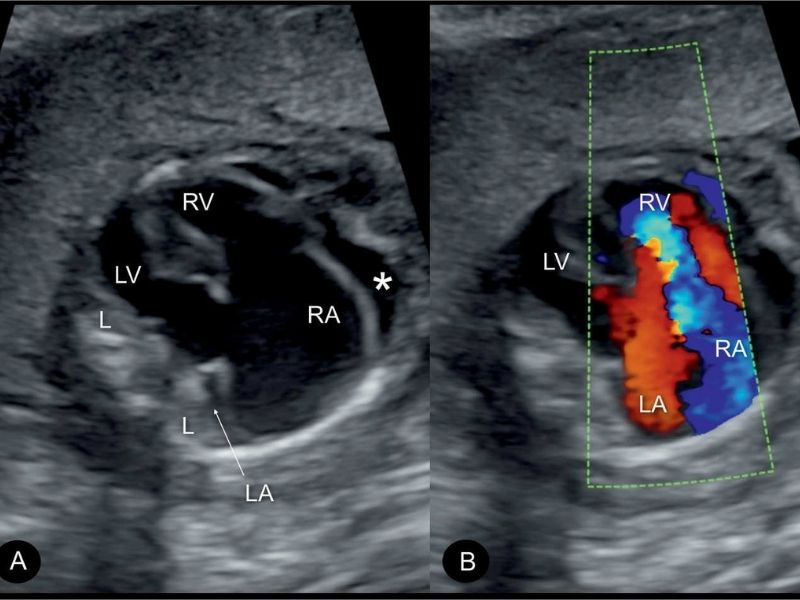

Khi siêu âm Doppler trong thai kỳ, bác sĩ có thể ghi nhận hở van 3 lá khi phát hiện dòng chảy ngược nếu vận tốc dòng chảy ngược từ 60 - 80 cm/giây trở lên và kéo dài ít nhất một nửa thì tâm thu trong giai đoạn thai nhi nghỉ ngơi. Sự xuất hiện của dòng ngược chiều (biểu hiện bằng màu sắc khác biệt và hiện tượng aliasing trên Doppler màu) là cơ sở quan trọng để xác định tình trạng hở van ba lá ở thai nhi.